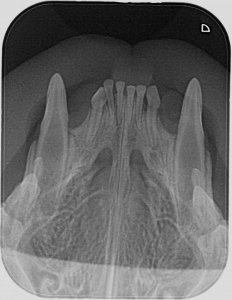

Ich hab zwar hier schon einige röntgenzahnbilder gesehen wo von Knochenabbau die rede war, deswegen hatte ich die Stellen markiert wo es (für mich ) auch so aussah, aber wahrscheinlich ist das in Ordnung so. Ich hoffe ja dass sich dazu noch jemand meldet und mir grünes Licht gibt.